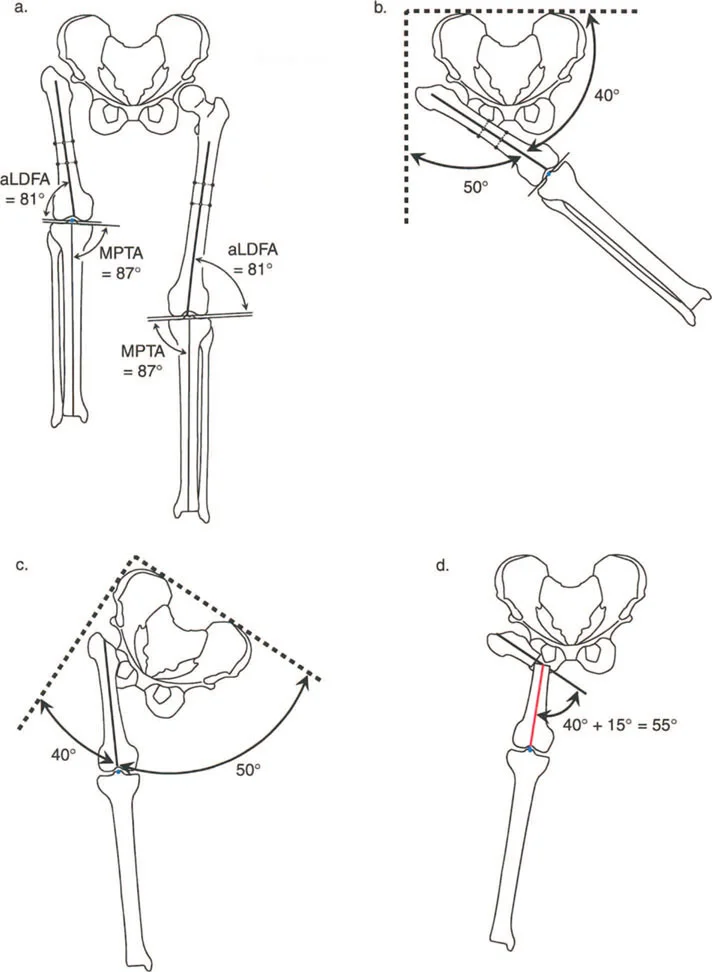

يُعد "المحور الميكانيكي" للطرف السفلي مفهومًا حيويًا. تخيل خطًا مستقيمًا يمتد من مركز رأس عظم الفخذ (في الورك) إلى مركز مفصل الكاحل. في الطرف السليم، يجب أن يمر هذا الخط تقريبًا عبر منتصف مفصل الركبة. هذا المحور هو الذي يحدد كيفية توزيع وزن الجسم عبر المفاصل أثناء الوقوف والمشي.

عندما ينحرف هذا المحور الميكانيكي عن مساره الطبيعي بسبب تشوه في أحد العظام، فإن الضغط على المفاصل يتوزع بشكل غير متساوٍ. على سبيل المثال، إذا كان المحور يمر كثيرًا عبر الجانب الداخلي للركبة (انحراف تقوس الساق - Varus)، فإن الغضروف في هذا الجانب سيتعرض لضغط مفرط ويتآكل بشكل أسرع، مما يؤدي إلى التهاب المفاصل والألم. والعكس صحيح إذا كان المحور يمر عبر الجانب الخارجي (انحراف الركبة الروحاء - Valgus).

* قياس الزوايا: قياس الزوايا المختلفة للمفاصل (مثل زاوية الفخذ الوحشية القريبة mLPFA وزاوية الفخذ الوحشية البعيدة mLDFA) ومقارنتها بالقيم الطبيعية.

مركز دوران الانحراف (CORA)

يعتبر CORA خاصية أساسية للتشوه في العظم. يُعرّف بأنه نقطة تقاطع خط المحور الميكانيكي (أو التشريحي) القريب وخط المحور الميكانيكي (أو التشريحي) البعيد.

* CORA الحقيقي: هو القمة التشريحية الفعلية للتشوه.

* CORA الحل (Resolution CORA): نقطة نظرية تُستخدم في التشوهات متعددة المستويات حيث تتقاطع المحاور القريبة والبعيدة النهائية، وقد لا تقع هذه النقطة داخل العظم نفسه.

محور تصحيح الزاوية (ACA)

بينما يعتبر CORA حقيقة تشريحية ثابتة، فإن ACA يقع جزئيًا تحت سيطرة الجراح. يمثل ACA النقطة المحورية التي يدور حولها الجزء البعيد من العظم لتحقيق التصحيح.

* الموضع الأمثل: يجب أن يكون ACA موجهًا بشكل عمودي على مستوى التشوه ويمر مباشرة عبر CORA.

مستوى قطع العظم (Osteotomy Level)

مستوى قطع العظم (الشق الجراحي) يقع بالكامل تحت سيطرة الجراح. تحدد العلاقة الهندسية بين مستوى قطع العظم، وACA، وCORA النوع الدقيق للتصحيح الناتج، وتحدد ما إذا كان سيحدث تشوه ثانوي غير مقصود (مثل الانزياح غير المرغوب فيه).

إن فهم العلاقة المكانية بين القطع، والمفصلة، وقمة التشوه هو سر التصحيح الخالي من العيوب. تحدد قواعد بالي لقطع العظم النتائج الميكانيكية لخطتك الجراحية:

القاعدة الذهبية الأولى: القطع والمفصلة عند مركز الانحراف

عندما يمر كل من قطع العظم وACA مباشرة عبر CORA، يتم تصحيح التشوه الزاوي بشكل مثالي. يتم استعادة المحور الميكانيكي، ولا يوجد انحراف في المحور الميكانيكي (MAD)، وتبقى أجزاء العظم القريبة والبعيدة متوازية تمامًا. هذا هو السيناريو المثالي، والذي غالبًا ما يتحقق بقطع عظم وتدي بسيط (فتح أو إغلاق) عند قمة التشوه.

القاعدة الذهبية الثانية: المفصلة عند مركز الانحراف والقطع بمستوى مختلف

في بعض الأحيان، قد يكون قطع العظم مباشرة عند CORA غير ممكن سريريًا بسبب سوء حالة الجلد، أو وجود أدوات جراحية سابقة، أو مشاكل في جودة العظم في منطقة الكردوس/الجذع. إذا بقي ACA عند CORA، ولكن تم إجراء قطع العظم عند مستوى مختلف (أقرب أو أبعد عن CORA)، فسيتم تصحيح التشوه الزاوي بالكامل. ومع ذلك، ستنزاح نهايات العظم عند موقع قطع العظم بالنسبة لبعضها البعض.

* النتيجة السريرية: يؤدي هذا إلى "نتوء" أو تعرج في المحور التشريحي، لكن المحور الميكانيكي العام وتوجيه المفصل يظلان متوائمين تمامًا.